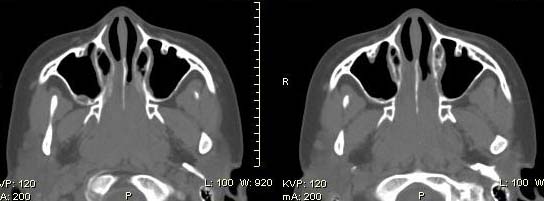

以下是引用随光逐影在2009-6-4 21:13:00的发言:[br]1)考虑鼻咽腺样体重度肥大。2)双侧鼻腔炎性改变。3)双侧上颌窦、双侧筛窦及左侧蝶窦炎症。

以下是引用zsl6918在2009-6-5 7:42:00的发言:[br]首先考虑鼻咽腺样体重度肥大,鉴别纤维血管瘤.强化有助明确.